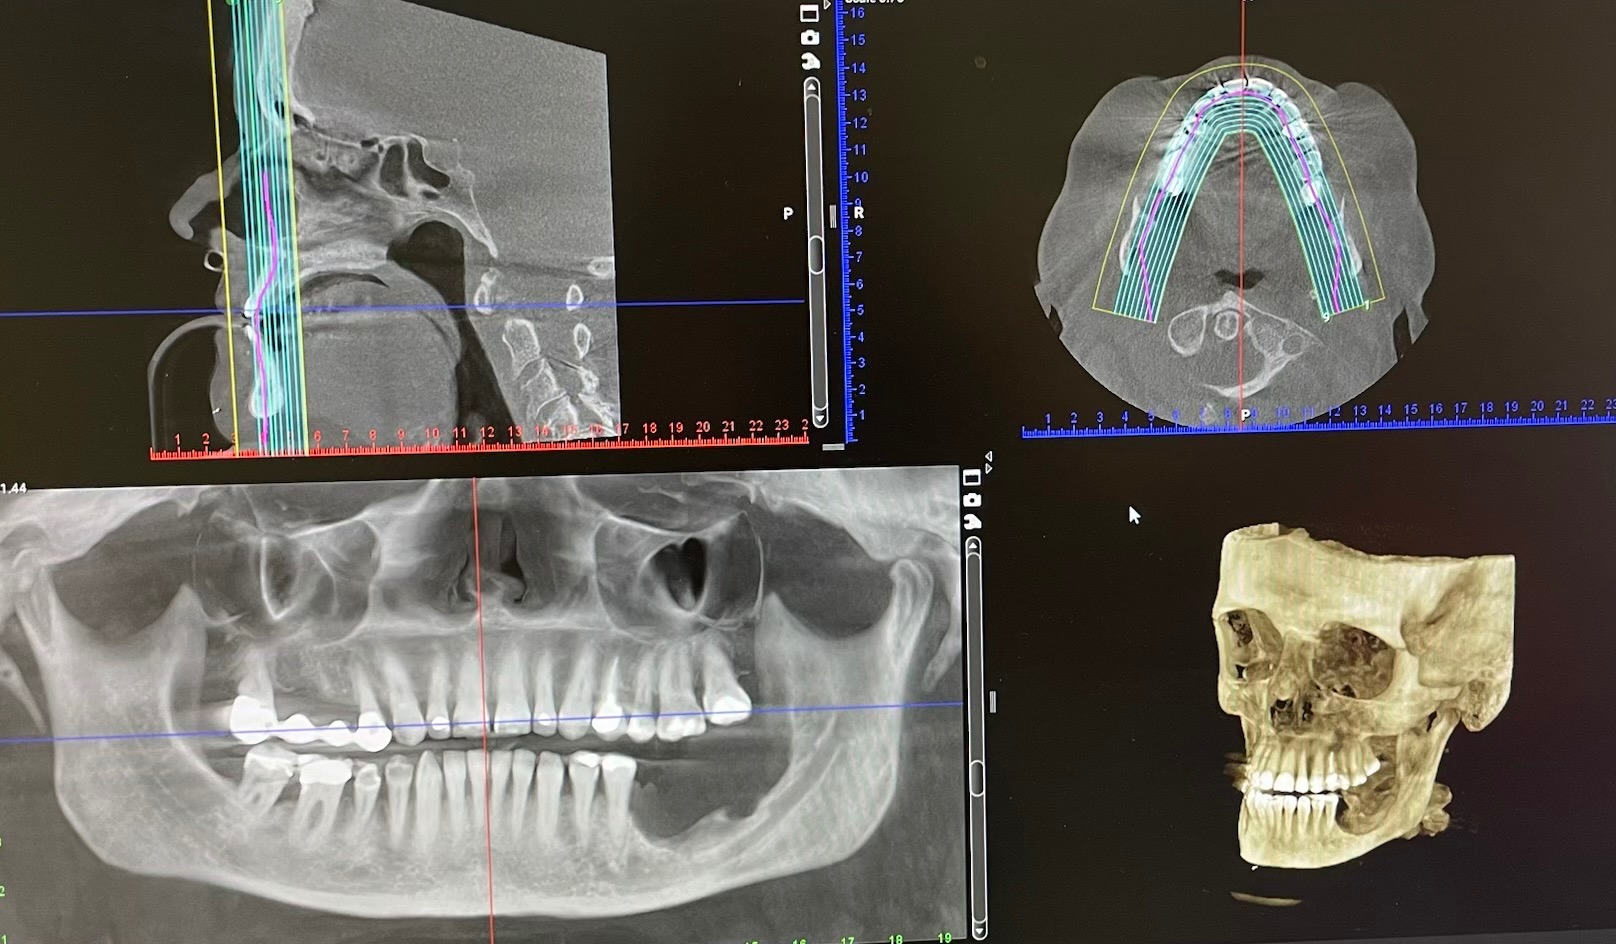

We are reaching out with heavy hearts to ask for help for our grandparents, who have spent over 60 years building a life together and supporting their family. Now, at 79 years old, they are facing overwhelming challenges that no one should have to endure alone. Grandpa is living with dementia and needs daily help with basic tasks, while Grandma is bravely fighting two forms of cancer. One of her cancers has severely deteriorated her jaw, making it impossible for her to eat normally. She has lost over 70 pounds and now needs constant assistance with everyday activities and preparing food.